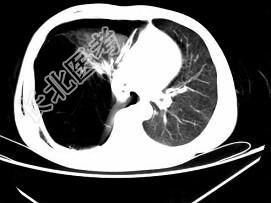

- 单项选择题男,32岁, 被车撞伤后1小时,请结合影像图像选择其最可能的诊断为 ( )

A、右侧气胸

B、右肺不张

C、右侧气胸并皮下纵隔气肿

D、右侧肺大疱并皮下纵隔气肿

E、支气管断裂